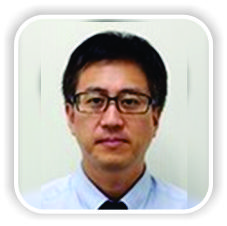

A 26-year-old man with Type III OI and a history of correction osteotomy and intramedullary Kirschner wire fixation in his right humerus at the age of 8 years felt gradually increasing pain in his humerus. His left upper limb and both lower limbs were not functional, and he lived in an electric wheelchair. He was unable to manually operate the wheelchair and instead moved it with a switch using his right hand. His right upper limb was his only functional extremity. He had developed humeral shaft non-union due to a broken Kirschner wire used in the previous operation. He was referred to our hospital and underwent internal fixation using an intramedullary elastic nail with an autogenous iliac bone graft. However, 2 years after the operation, bony union was not achieved and elastic nail breakage had occurred, and he complained of pain and limitation of activity (Fig. 1). He underwent a re-operation for his humeral non-union using a locking plate to achieve rigid fixation. Since his humeral shaft was extremely narrow with severe deformity, we used a locking plate for the mandibular bone, which was contoured to fit the medial side of the humeral shaft (Fig. 2). Bony union was achieved, and he became free from pain and returned to his pre-injury activity with no symptoms. No implant failure or refracture of his humeral shaft had occurred 4 years later, but a new fracture line was found in radiographs of the distal part of the non-union (Fig. 3). We used a cast to fix the new fracture for 9 weeks and then a splint for 4 weeks.He recovered well, and at the time of this writing, he was maintaining normal function of the right upper limb and was able to perform activities of daily life without problems.

Type III OI causes severe bone fragility, and multiple fractures are usually present at birth. These patients develop a severely shortened height and progressive deformity of the limbs and spine with age. Due to their poor bone quality, patients with OI are prone to fractures. These fractures are often difficult to manage because their narrow bone shafts provide limited surface area for contact of prostheses and because bowing adds mechanical stress. In addition, poor bone quality disturbs most treatment plans, especially surgical treatment. Although most low-energy fractures in patients with OI may heal uneventfully, some will fail to achieve bony union. Non-union is more common in patients with than without OI, and patients with Sillence Type III OI are at particularly high risk of non-union. Studies have estimated that approximately 20% of patients with OI develop non-union [4, 5, 6]. In one study, the rate of non-union was slightly lower in patients treated surgically than in those treated conservatively, but the difference was not statistically significant [7]. To obtain good bone fusion, fixation with intramedullary elastic nailing should be considered for femoral non-union complicated by OI [8]. The use of sandwich allograft struts is a durable, safe method for the stabilization and healing of persistent long bone non-union in patients with OI [9]. Intramedullary fixation with autogenous bone graft, combined with concomitant realignment if necessary, is the first-choice treatment for non-union without significant segmental bone loss. Similarly, shortening with an autogenous bone graft and intramedullary fixation is suggested for small gap non-union [10]. In the present case, we selected a locking plate for treatment due to the short diameter of the medullary cavity in the humeral shaft, the hard deformation, the hypertrophic non-union, and the poor bone quality. We used a matrixmandible reconstruction plate “DePuy Synthes, West Chester, PA, USA”. This plate was easy to bend and could be adapted to this case. In addition, this plate was suitable for the patient’s short bone transverse diameter because the screw diameter was also small. The patient’s humeral deformation was hardly a hindrance in his daily life before the development of the non-union. We attempted to fix the bone with a locking plate without correction osteotomy. Hanke et al. [11] reported that the locking plate technique was successful as a salvage procedure in a rare case of adult OI presenting with a femoral fracture. The advantage of using a locking plate is that screws with angular stability are evenly distributed throughout the load without concentrating at one contact point between the bone and the screw. If the fixing force of a conventional plate is lost, it usually starts with a single screw and spreads from there to other screws. The same phenomenon does not occur in a locking screw. Compared with conventional plate constructs, locking plates have mechanical advantages and are thus useful in patients with osteoporosis [12, 13]. Although the current patient was young, his condition was accompanied by bone fragility; locking plates are also useful in such cases. An asymptomatic slight fracture line developed during the 4 years follow-up period. No deterioration was observed by careful follow-up, and the patient attained a partial cure. Although fixation breakdown did not occur, slight screw loosening was observed on X-ray examination. This was not a problem at the time of the present writing, but careful follow-up is necessary.